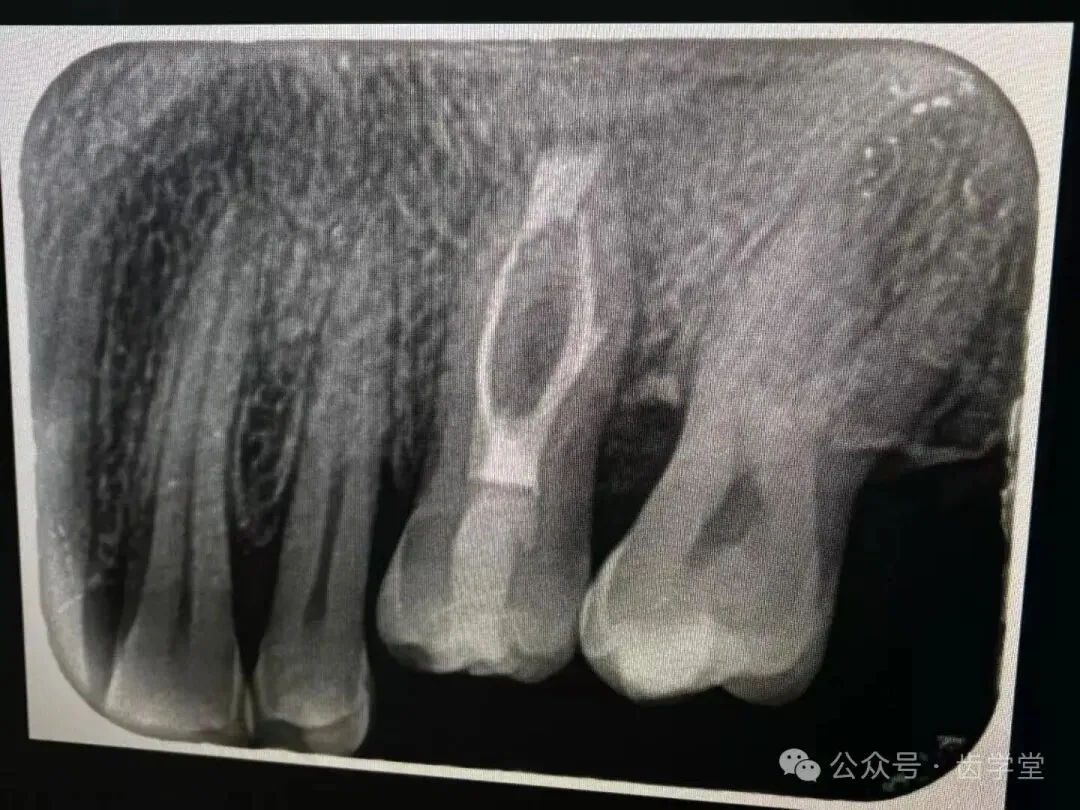

5. 自体牙移植的适应症和禁忌症及其把控;

8. 自体牙移植的术前检查、评估和准备;

17.牙周膜保护在自体牙移植的重要性;

26.上颌后牙窦嵴距不足时处理方法;

27.下颌后牙管嵴距不足时处理方法;